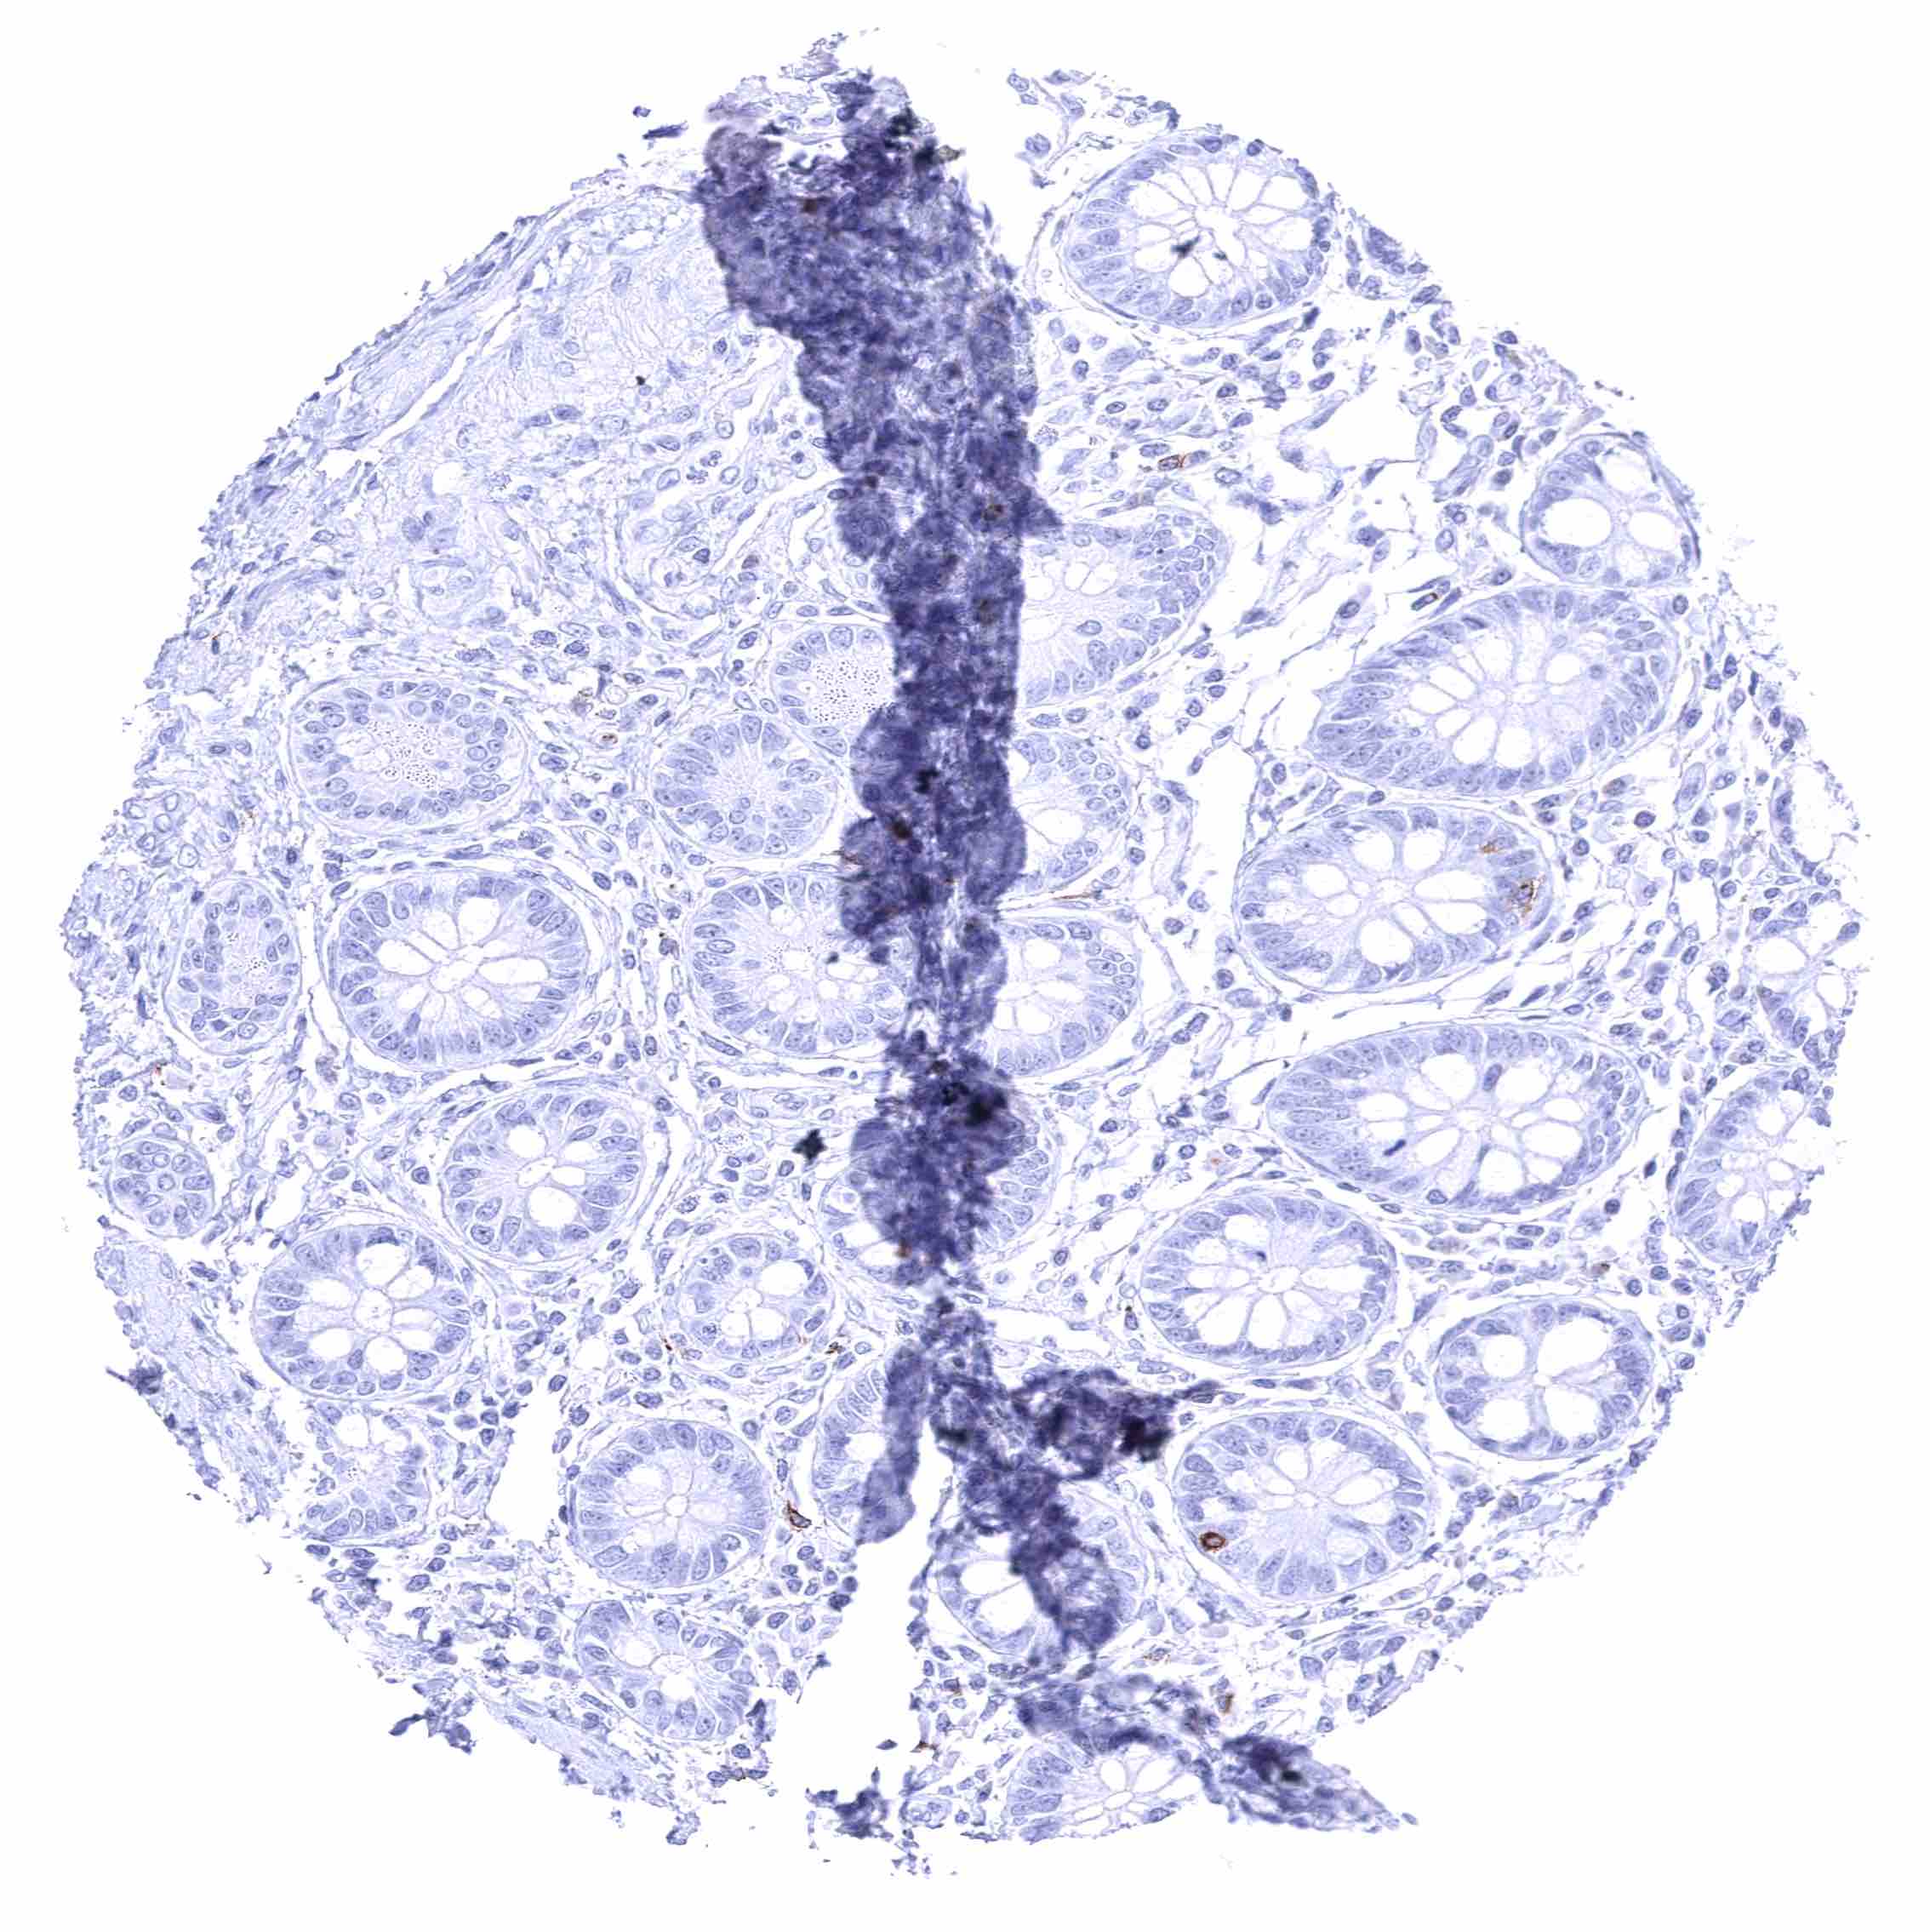

Appendix, mucosa – Epithelial cells are CD70 negative. Distinct CD70 positivity of a fraction of lymphocytic cells.

Appendix, muscular wall